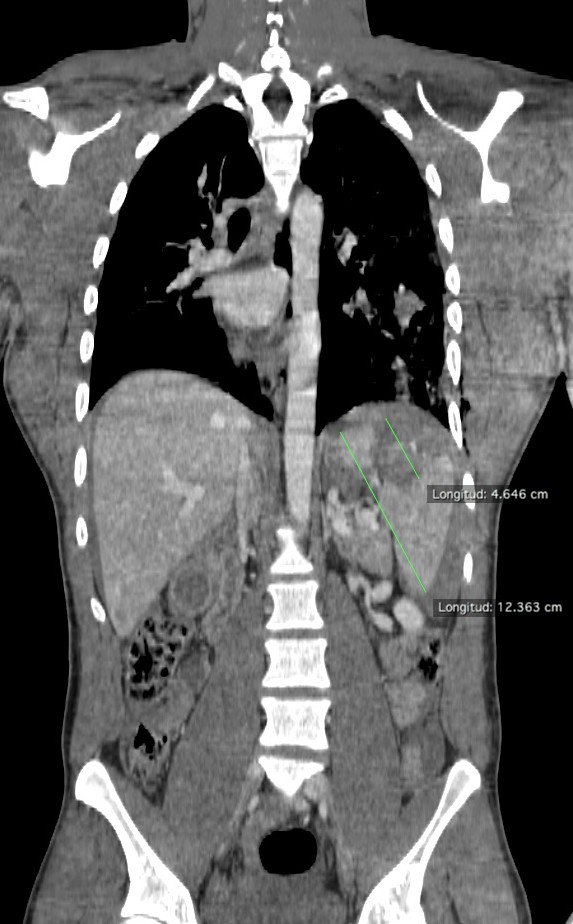

Varón jóven que acude a urgencias tras accidente de moto. Presenta dolor acusado en flanco izquierdo.

Ante estos hallazgos, estamos ante un traumatismo esplénico grado III. Con la edad del paciente y los indicios de inestabilidad hemodinámica, se decidió tratamiento mediante embolización arterial.

TC: Es la técnica de elección, nos permite establecer la graduación de la lesión esplénica así como descartar lesiones en otros orgános, retroperitoneo y pared abdominal. El desarrollo y uso de la TC ha permitido el tratamiento conservador de la lesiones espléncias, así como dotar de mayor información y seguridad a los cirujanos en el caso de ser necesaria una intervención quirúrgica.

Debe hacerse en fase dual, la fase portal detecta mejor el sangrado activo y las lesiones parenquimatosas como contusiones o laceraciones, mientras que la fase arterial es útil para diagnosticar lesiones vasculares como un seudoaneurisma o fístulas.

Si existe estabilidad hemodinámica el tratamiento es no quirúrgico. La embolización arterial esplénica se usa para lesiones esplénicas de consideración en pacientes estables, aunque cada vez más se usa también en casos de alto grado de lesión con inestabilidad hemodinámica.

- Requieren intervencionismo: pacientes con inestabilidad hemodinámica y Grado V

- Individualizar: Grado III y IV